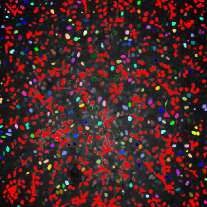

Additionally, two synthetic data generation methods between CycleGAN and SpCycleGAN from the same synthetic binary image are compared in Figure 4. Here, the synthetic binary image is overlaid on the synthetic microscopy image and labeled in red. It is observed that our spatial constraint loss reduces the location shift of nuclei between a synthetic microscopy image and its synthetic binary image. Our realistic synthetic microscopy volumes from SpCycleGAN can be used to train our modified 3D U-Net.

To make this clear, segmentation results were color coded using 3D connected component labeling and overlaid on the original volumes. The method from [20] cannot distinguish between nuclei and non-nuclei structures including noise. This is especially recognizable from segmentation results of Data-I in which multiple nuclei and non-nuclei structures are colored with the same color. As can be observed from Figure 6 and 6, segmentation masks are smaller than nuclei size and suffered from location shifts. Conversely, our proposed method shown in Figure 6 and 6 segments nuclei with the right shape at the correct locations.